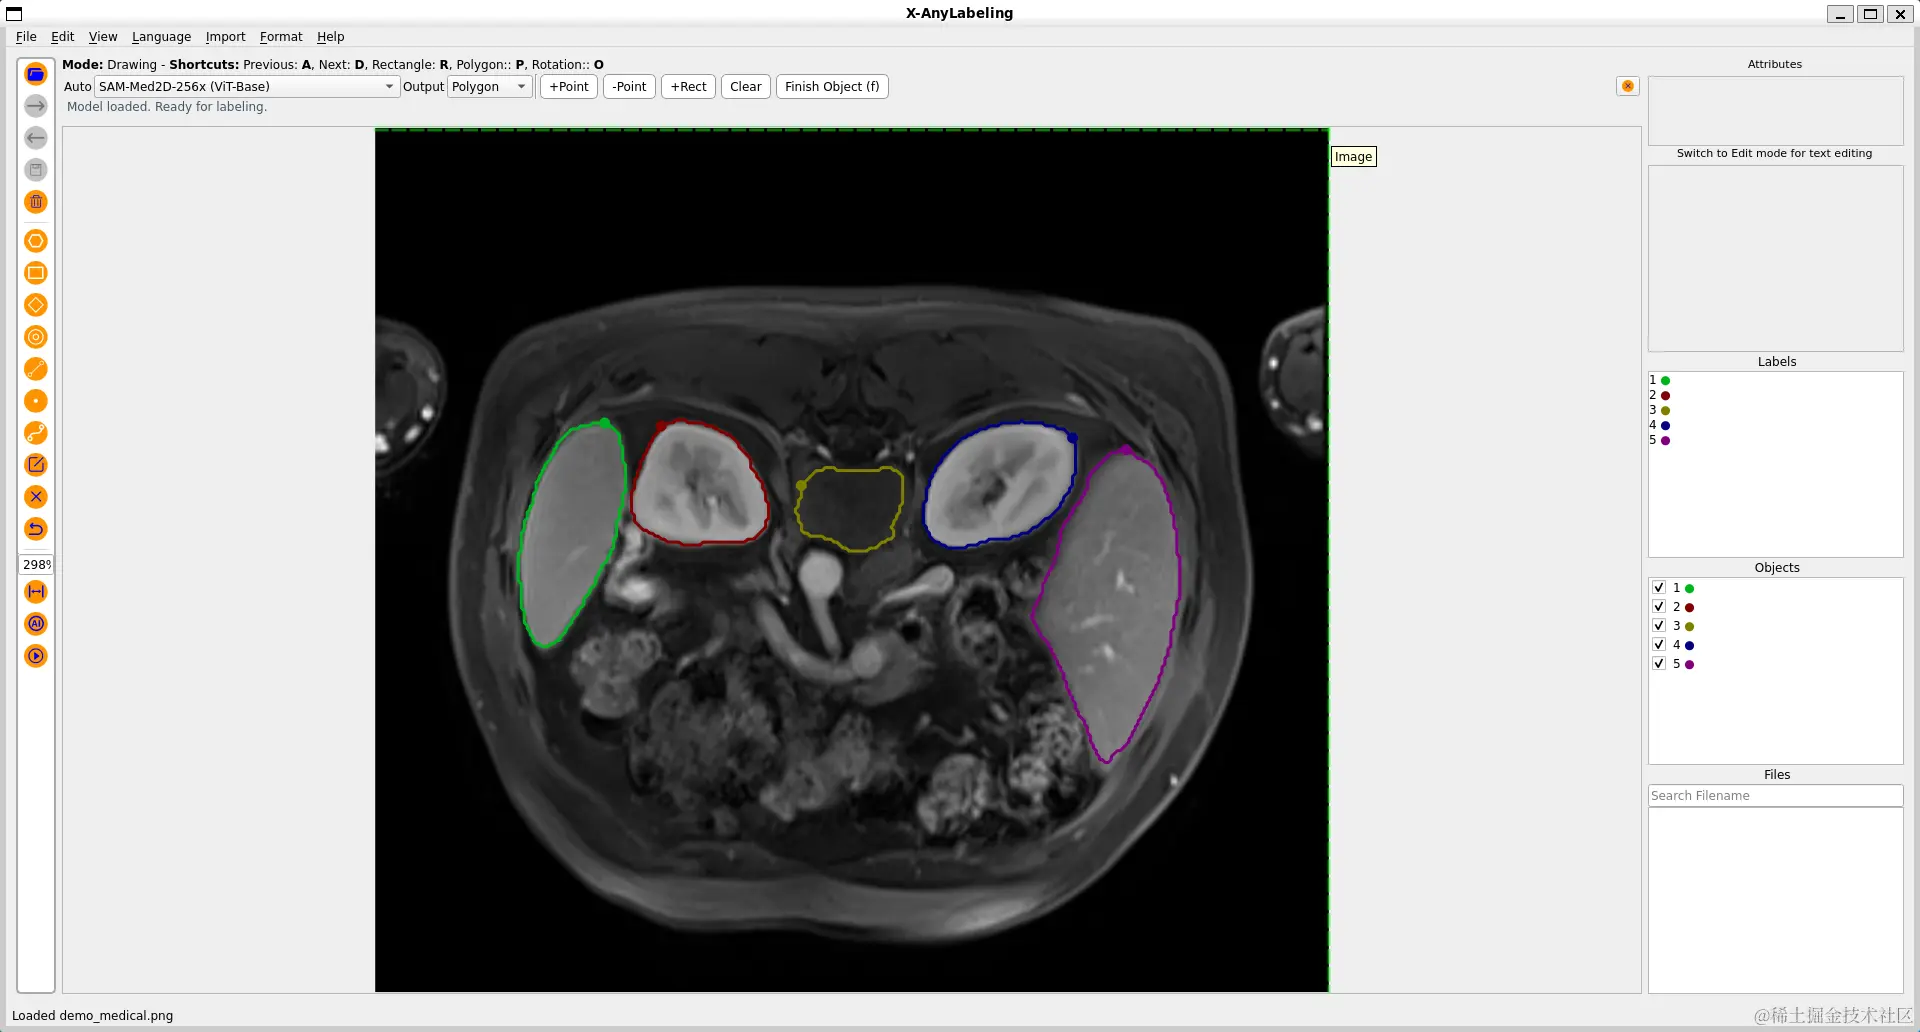

更进一步地,针对医学图像场景,X-AnyLabeling中同样提供了多种基于 SAM 微调的高精度模型,包括:

• SAM-Med2D: 通用医疗图像分割一切模型;

• LVM-Med ISIC SAM:皮肤病灶分割一切模型;

• LVM-Med BUID SAM:超声乳腺癌分割一切模型;

• LVM-Med Kvasir SAM:结直肠息肉分割一切模型;

最后,工具内还内置了 yolov5-SAMYOLOv8-EfficientvitSAM 模型,可以为原始的分割模型提供更加精细化的分割结果!